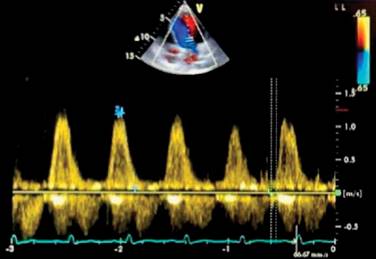

In the echocardiographic assessment of the diastolic function of the left ventricle, dilation of the left atrium was found. In the echocardiogram performed at 10 days, at seven, and at 12 months, measurements that establish reversibility of the atrial dimensions were found. The filling pattern was normal during the evolution of the pathology, and the E/A ratio was reported to be 1.03, with the normal range of said value being 0.75 up to 1.5. The assessment of systolic function using tissue Doppler was abnormal, manifesting alterations in the contractility of the right ventricle. The right atrium showed dilation until reaching reversibility of its structure; the maximum velocity of the tricuspid valve maintained average values of 2.6 m/sec, in addition to the presence of a dicrotic notch when measuring pulmonary artery flow using Doppler. Concluding that the patient had systolic and diastolic dysfunction (Figure 6) with preserved cardiac output during the acute stage of the condition, subsequent changes suggestive of acute pulmonary embolism that would be corroborated by CTPA (Table 1).

The initial LVEF was 36%, and 48 hours later, it was 47% (Figure 1). The echocardiogram showed important dilation of the left ventricle (Figure 2). The echocardiographic controls performed on the tenth day, at seven and 12 months, showed recovery and normal LVEF, demonstrating complete reversibility at 10 days that continues up to one year (Figure 3). There was no compromise in cardiac output according to measurements in the five echocardiograms performed. The cardiac index was calculated using the Dubois cardiac index estimation formula; the cardiac index was not altered during the development of the pathology.22 GLS is also used to assess left ventricular systolic function in patients with septic shock. It detects subtle changes in myocardial contractility and is more sensitive and accurate in evaluating systolic ventricular function compared to LVEF. We obtained a GLS of -14% initially (Figure 4); in the 12th month of echocardiographic control, normalization of the values was found with a GLS of -20.6% (Figure 5), therefore recovery of systolic function, which is considered normal at values of -18% to -20%. Measurement of variables through direct methods was not possible.